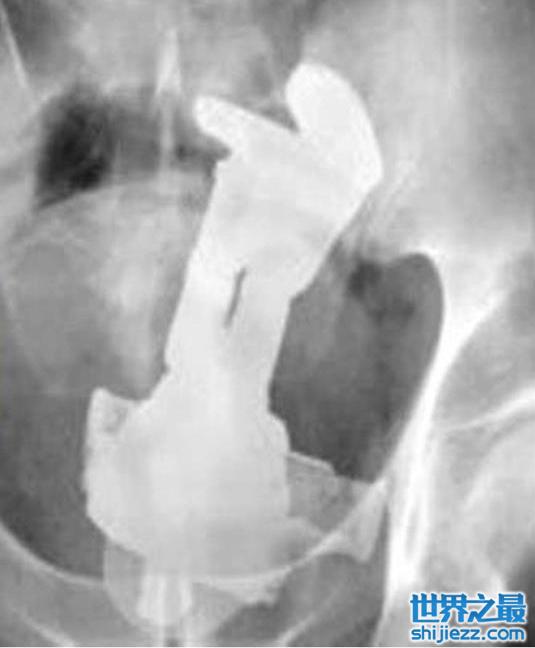

而且在印度还有一位62岁的男子,因为肚子疼痛不已就医,没想到医生竟然在他肠子里面,找到一个21厘米高的钢杯。而男子回想之后,认为他在几天前被歹徒抢劫过,而他在意外的当下被打昏,接着醒来以后屁股跟腹部都有疼痛感,认为是歹徒所为。

但至于这个男子所说的真伪,医生们只是笑笑不予置评!